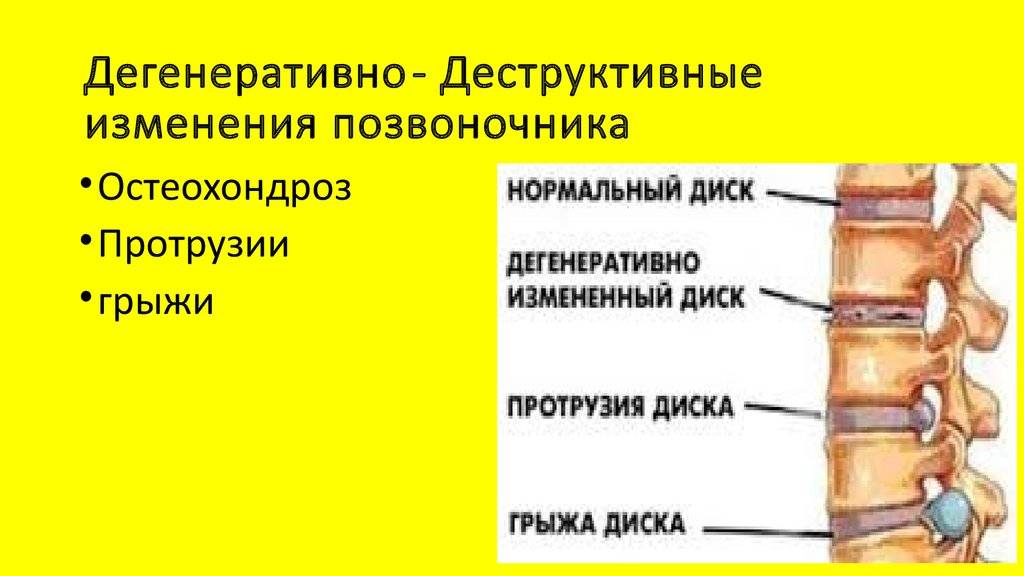

Мрт картина дегенеративно дистрофических изменений пояснично крестцового отдела позвоночника